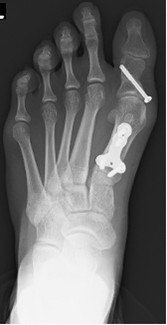

外反母趾の手術的治療

術前レントゲン写真

術後レントゲン写真

外反母趾の写真(左術後、右術前)